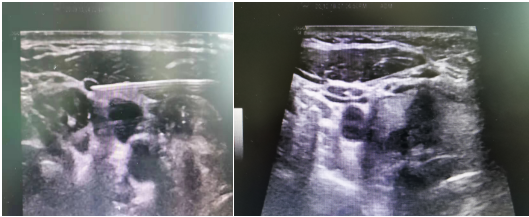

圖中每個(gè)穿刺可見針尖在淋巴結(jié)內(nèi),保證穿刺結(jié)果的準(zhǔn)確性,同時(shí)避免了損傷大血管

穿刺結(jié)果顯示雙側(cè)甲狀腺乳頭狀癌伴有雙側(cè)側(cè)頸區(qū)淋巴結(jié)轉(zhuǎn)移,屬于早期轉(zhuǎn)移